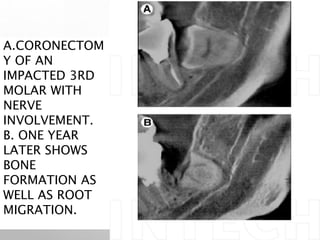

A.CORONECTOM

Y OF AN

IMPACTED 3RD

MOLAR WITH

NERVE

INVOLVEMENT.

B. ONE YEAR

LATER SHOWS

BONE

FORMATION AS

WELL AS ROOT

MIGRATION.